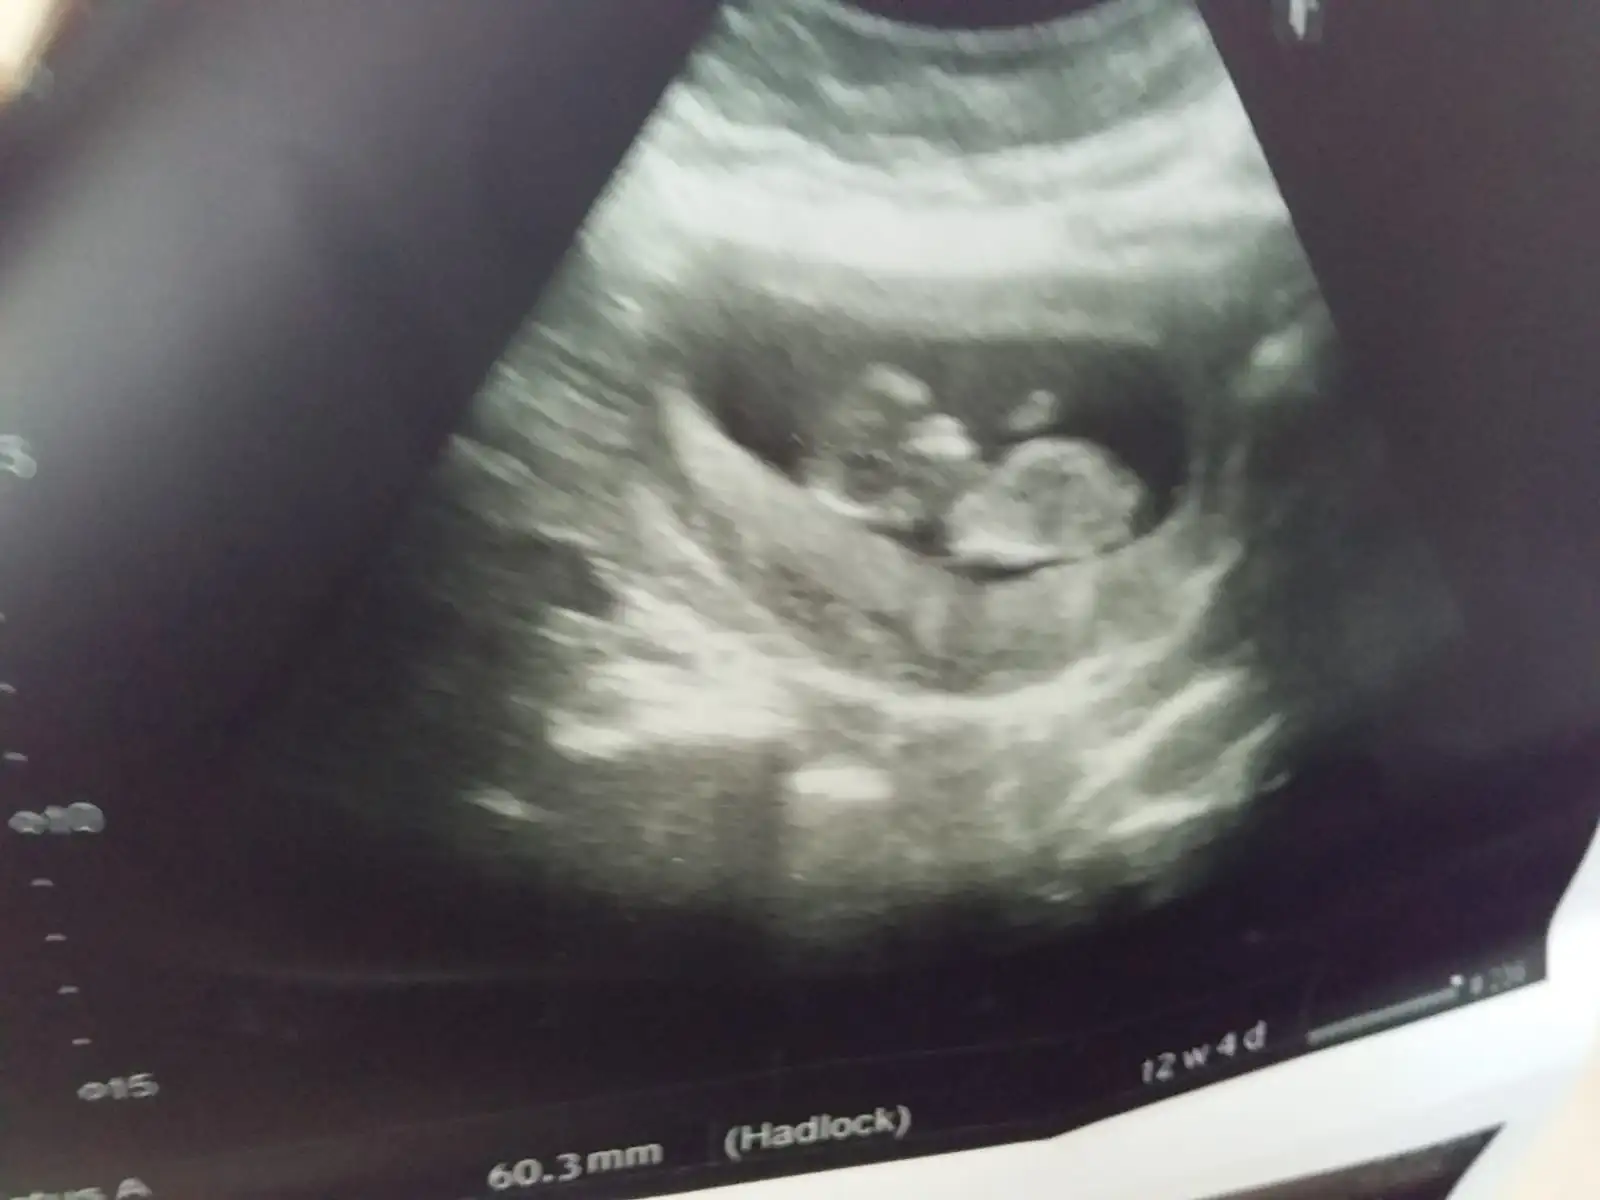

Bana da bakar mısınız tam 8+0 karından bakıldı

Bu birz buyuk ama olsun bi tahminde bulunmmi istersen erkege benzetdimMaalesef bu ilk ve tek

Am sen yine 11 12 13 hafta resimleri olunca at kesin yorumlarim